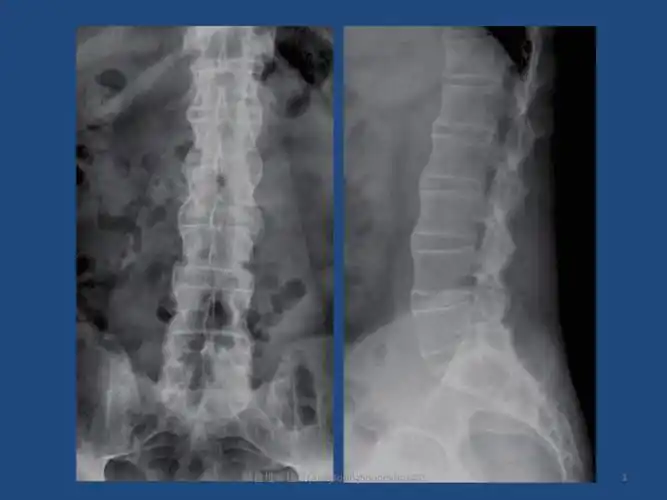

强直性脊柱炎ankylosingspondylitisas课件